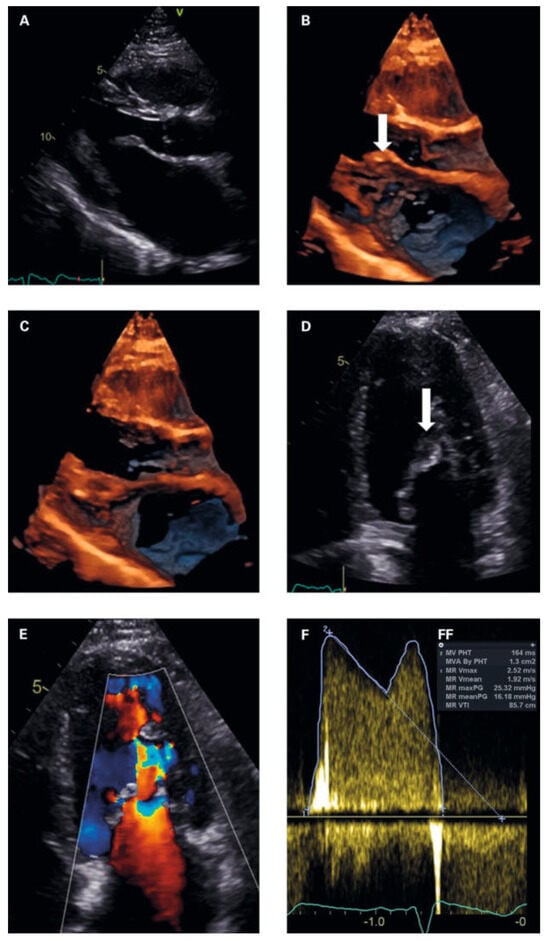

Figure 3. (a) Parasternal long axis in diastole. Normal sized left ventricle. dilated left atrium. thickened anterior mitral leaflet with typical hockey stick appearance (arrow) and restricted posterior leaflet. (B, C) 4d imaging parasternal long axis in diastole (3B) and systole (3C) showing doming and extensive subvalvular thickening of the mitral apparatus. (D) apical 4 chamber view at diastole. Arrow subvalvular doming and thickening. (e) Colour doppler at diastole showing subvalvular flow increase with PiSa phenomenon. (F) Continous wave doppler measurements of the mitral valve gradients. (FF) Measurements mitral valve area and gradients.

To exclude left-heart disease as a possible cause of the congested bronchial vessels and the alveolar haemorrhage syndrome, first transthoracic and later transoesophageal echocardiography were performed. The main finding was a grotesque doming of thickened mitral leaflets with a severe subvalvular mitral stenosis (transthoracic echocardiography figure 3A–F and transoesophageal echocardiography figures 4A–D; mean pressure gradient 16.2 mm Hg, reference <5 mm Hg, at a heart rate of 82/min, calculated mitral valve area by pressure half-time method 1.3 cm2, reference >1.5 cm2; figure 3f; planimetry of mitral valve area 0.74 cm2 in TOE approach, figure 4d+e) and severe mitral regurgitation with pulmonary vein backflow due to restricted leaflet motion (fig. 4a). The right ventricular / right atrial pressure gradient across the tricuspid valve could not be obtained.

Transthoracic and transoesophageal 4D imaging revealed extensive fusion of thickened and shortened chordal structures extending down to the papillary muscles, a shortened posterior leaflet and a prolonged and entirely thickened anterior leaflet with restricted mobility, and mild calcification (fig 3 and fig 4), adding up to a Wilkins Score of 13 points (range 4–16).